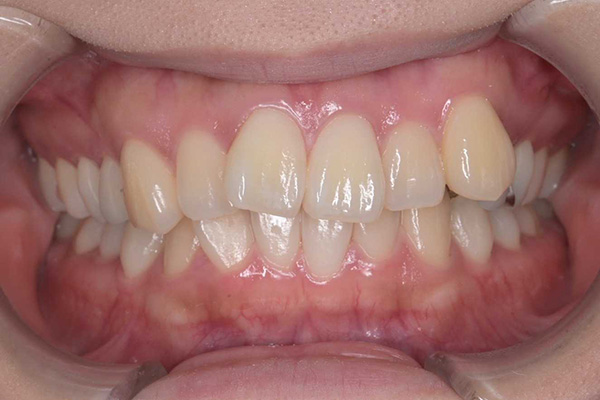

① セラミック治療と矯正治療

治療前

治療後

年代・性別

20代 女性

お悩み

八重歯が気になる

治療内容

矯正治療(ワイヤー)

セラミック治療

治療期間・回数

2年

費用

130万

リスク・副作用

根本的な歯列不正や噛み合わせの改善を目指す場合、治療期間が長くなるのが一般的です。見た目を整えるために天然歯を削って土台を作るため、一度削った歯は元に戻せません。